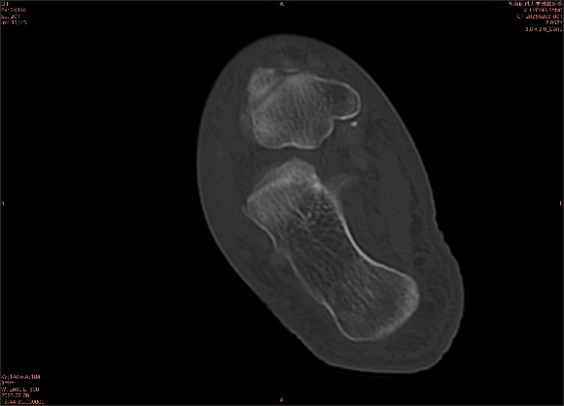

舉例圖像

圖1

專業(yè)解釋看不懂沒關(guān)系,大家看圖1和圖2就可以了,這是同一個(gè)患者跟骨的磁共振和CT圖像,圖1的紅色箭頭指示的黑線就是磁共振圖像顯示的骨折線,一目了然。而對比圖2的CT圖像上并未顯示異常。

這下大家明白了吧,如果懷疑隱匿性骨折優(yōu)先選擇磁共振檢查